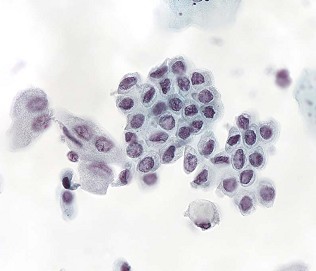

Кровяные клетки в моче при гематерии

- гематурия может быть невидимой невооруженным глазом (так называемая микрогематурия) и выявляться лишь при микроскопическом исследовании осадка мочи; встречается микрогематурия у 20-25% больных, страдающих от аденомы предстательной железы;

- у 15-18% больных наблюдается выраженная гематурия (макрогематруия) — кровь окрашивает мочу в красный цвет;